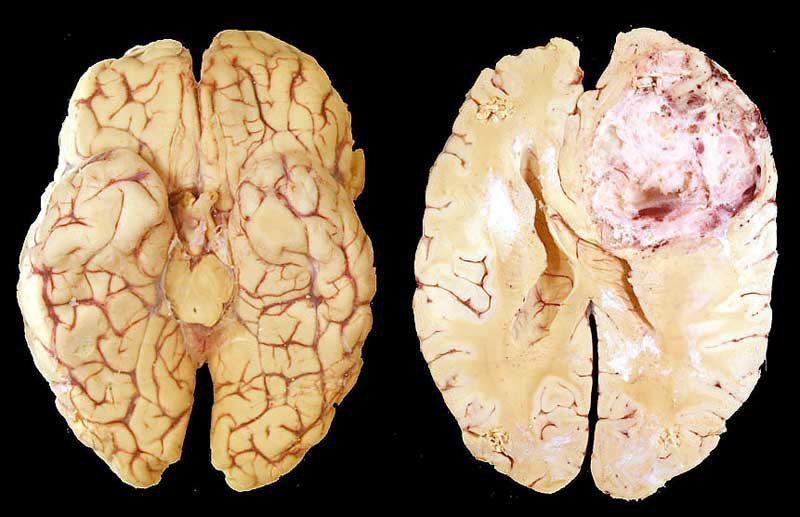

U nguyên bào thần kinh là một loại khối u ác tính xuất hiện ở trẻ em và người lớn. Đây là những khối u chưa trưởng thành, không biệt hóa. U nguyên bào thần kinh là những khối u trung gian và u hạch là những biến thể lành tính của u nguyên bào thần kinh; gọi chung là u mào thần kinh. Các triệu chứng lâm sàng của bệnh u nguyên bào thần kinh phụ thuộc vào vị trí nguyên phát của u và hình thức di căn của bệnh. Các triệu chứng phổ biến nhất là đau bụng, cảm giác khó chịu, dễ kích thích, chán ăn và cảm giác no do khối u ở bụng.

Tùy thuộc vào vị trí tế bào mà các loại u nguyên bào thần kinh đệm phát sinh, chúng sẽ có tên gọi khác nhau bao gồm u nguyên bào thần kinh đệm, u tế bào thần kinh đệm, u nguyên bào thần kinh đệm đa dạng (glioblastoma multiforme).